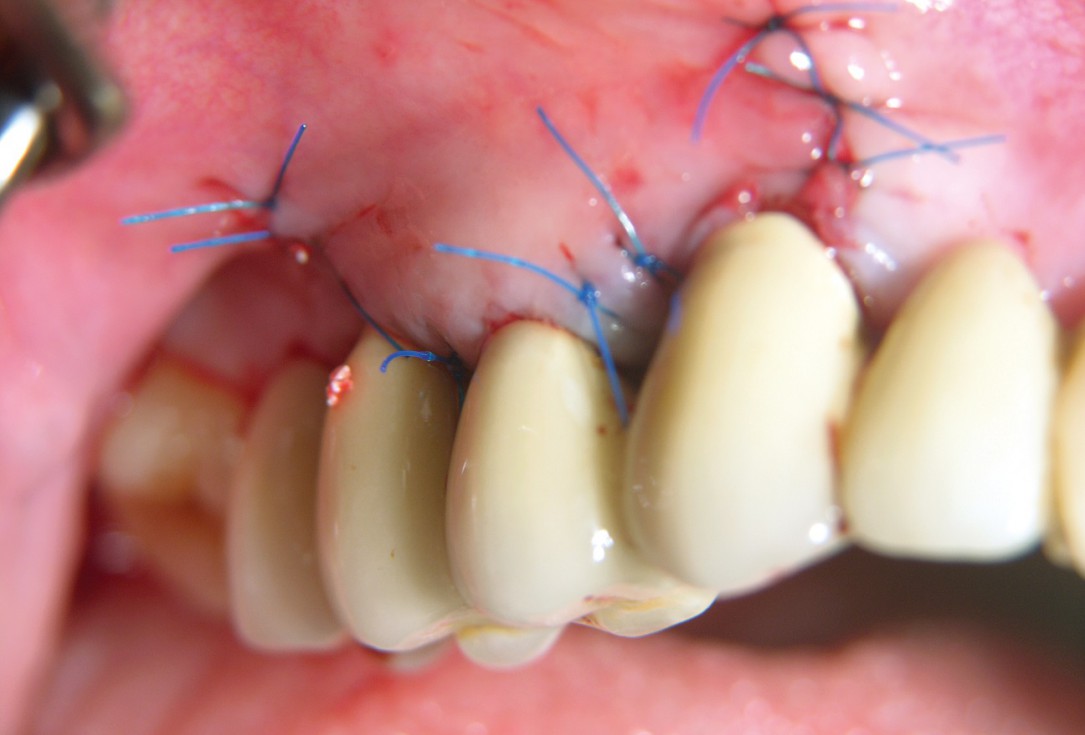

07/10 - Primary wound closure.GTR for the treatment of a deep three-dimensional intrabony defect using cerabone®, collprotect® membrane and Straumann® Emdogain® - Dr. T. Schwaar